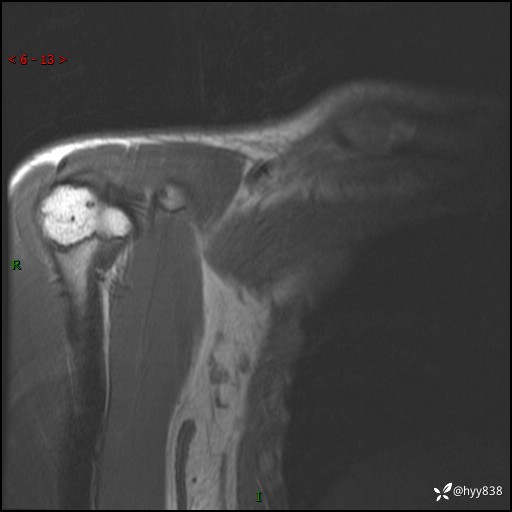

MRI(cor T1WI+T2WIfs+axi T2WIfs)